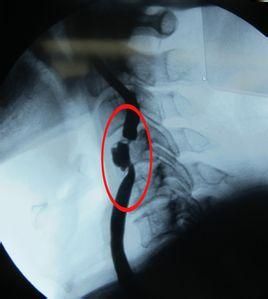

手術

嚴重的頸動脈狹窄有時需要做頸動脈內膜剝脫術或支架手術。